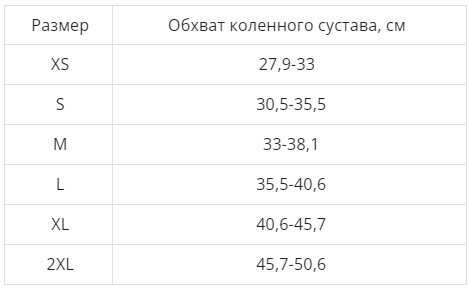

Эластичный циркулярный бандаж с отверстием над коленной чашечкой выполнен из гипоаллергенной нити с керамическим напылением, усилен двумя парами боковых пластинчатых пружинных ребер жесткости.

Характеристики